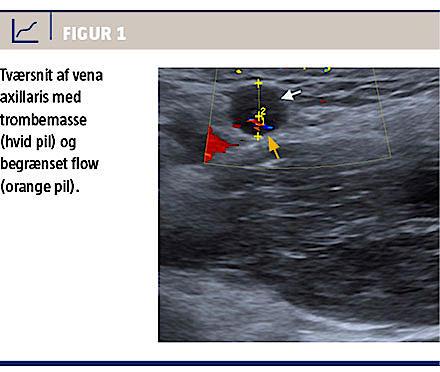

En akut UL-skanning af venstre arm med farve-Doppler viste massiv trombedannelse fra overgangen mellem vena brachialis og vena axillaris centralt til indgangen til vena brachiocephalica samt en PM-elektrode i tromben. På Figur 1 ses trombemasse i vena axillaris.

Billede